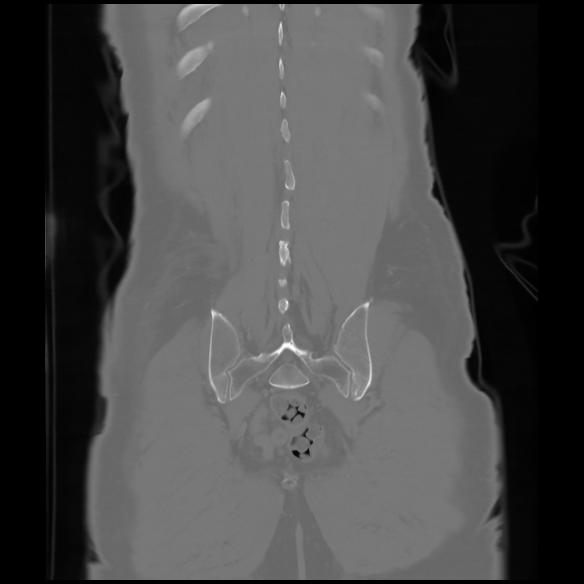

6 CUERPO,CE,Coronal,3.000,CUERPO,Coronal,